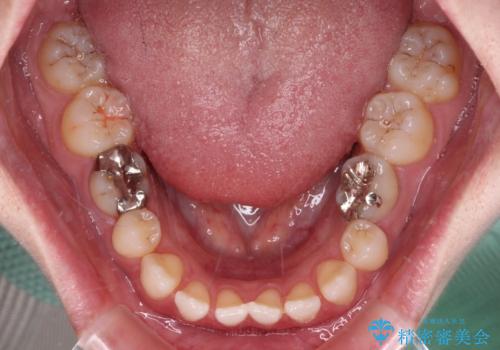

すきっ歯をインビザラインできれいな歯並びに改善

- 前歯の隙間を気にして来院された患者様です。

隙間や叢生の程度はそれほど著しいものではなかったので、インビザラインでもワイヤー矯正でも対応可能でしたが、極力目立たない装置を希望されたため、インビザラインにて矯正治療を行うこととしました。